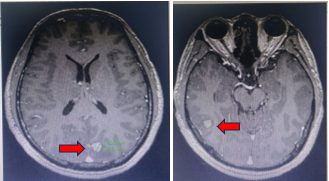

Chụp cộng hưởng từ sọ não 1/10/2019 (sau điều trị)

Hình 5: Các tổn thương não thứ phát biến mất sau xạ phẫu Gamma Knife.